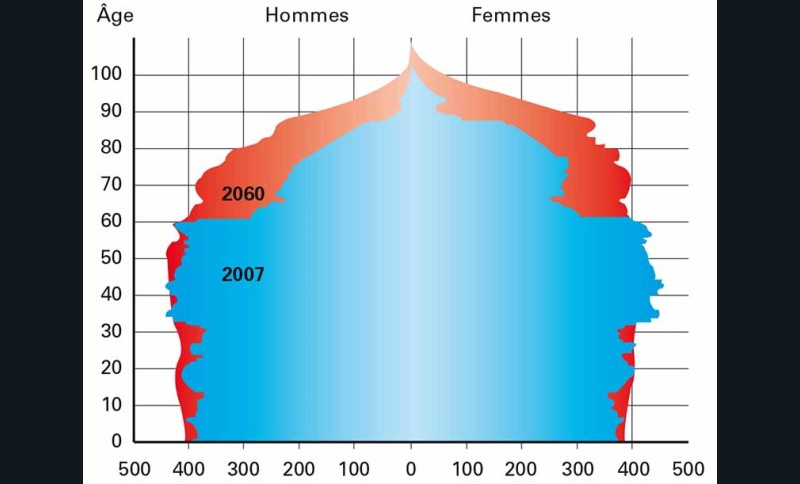

Dès aujourd’hui, la France en plein « papy-boom » doit relever le défi d’une population qui ne cesse d’augmenter en nombre et en âge. Les données de l’INSEE (1) prévoient une croissance importante du nombre de personnes de plus de 60 ans jusqu’en 2035 puis une hausse plus mesurée jusqu’en 2060. La France serait alors composée de 73 millions d’habitants dont un sur trois aurait plus de 60 ans (fig. 1).